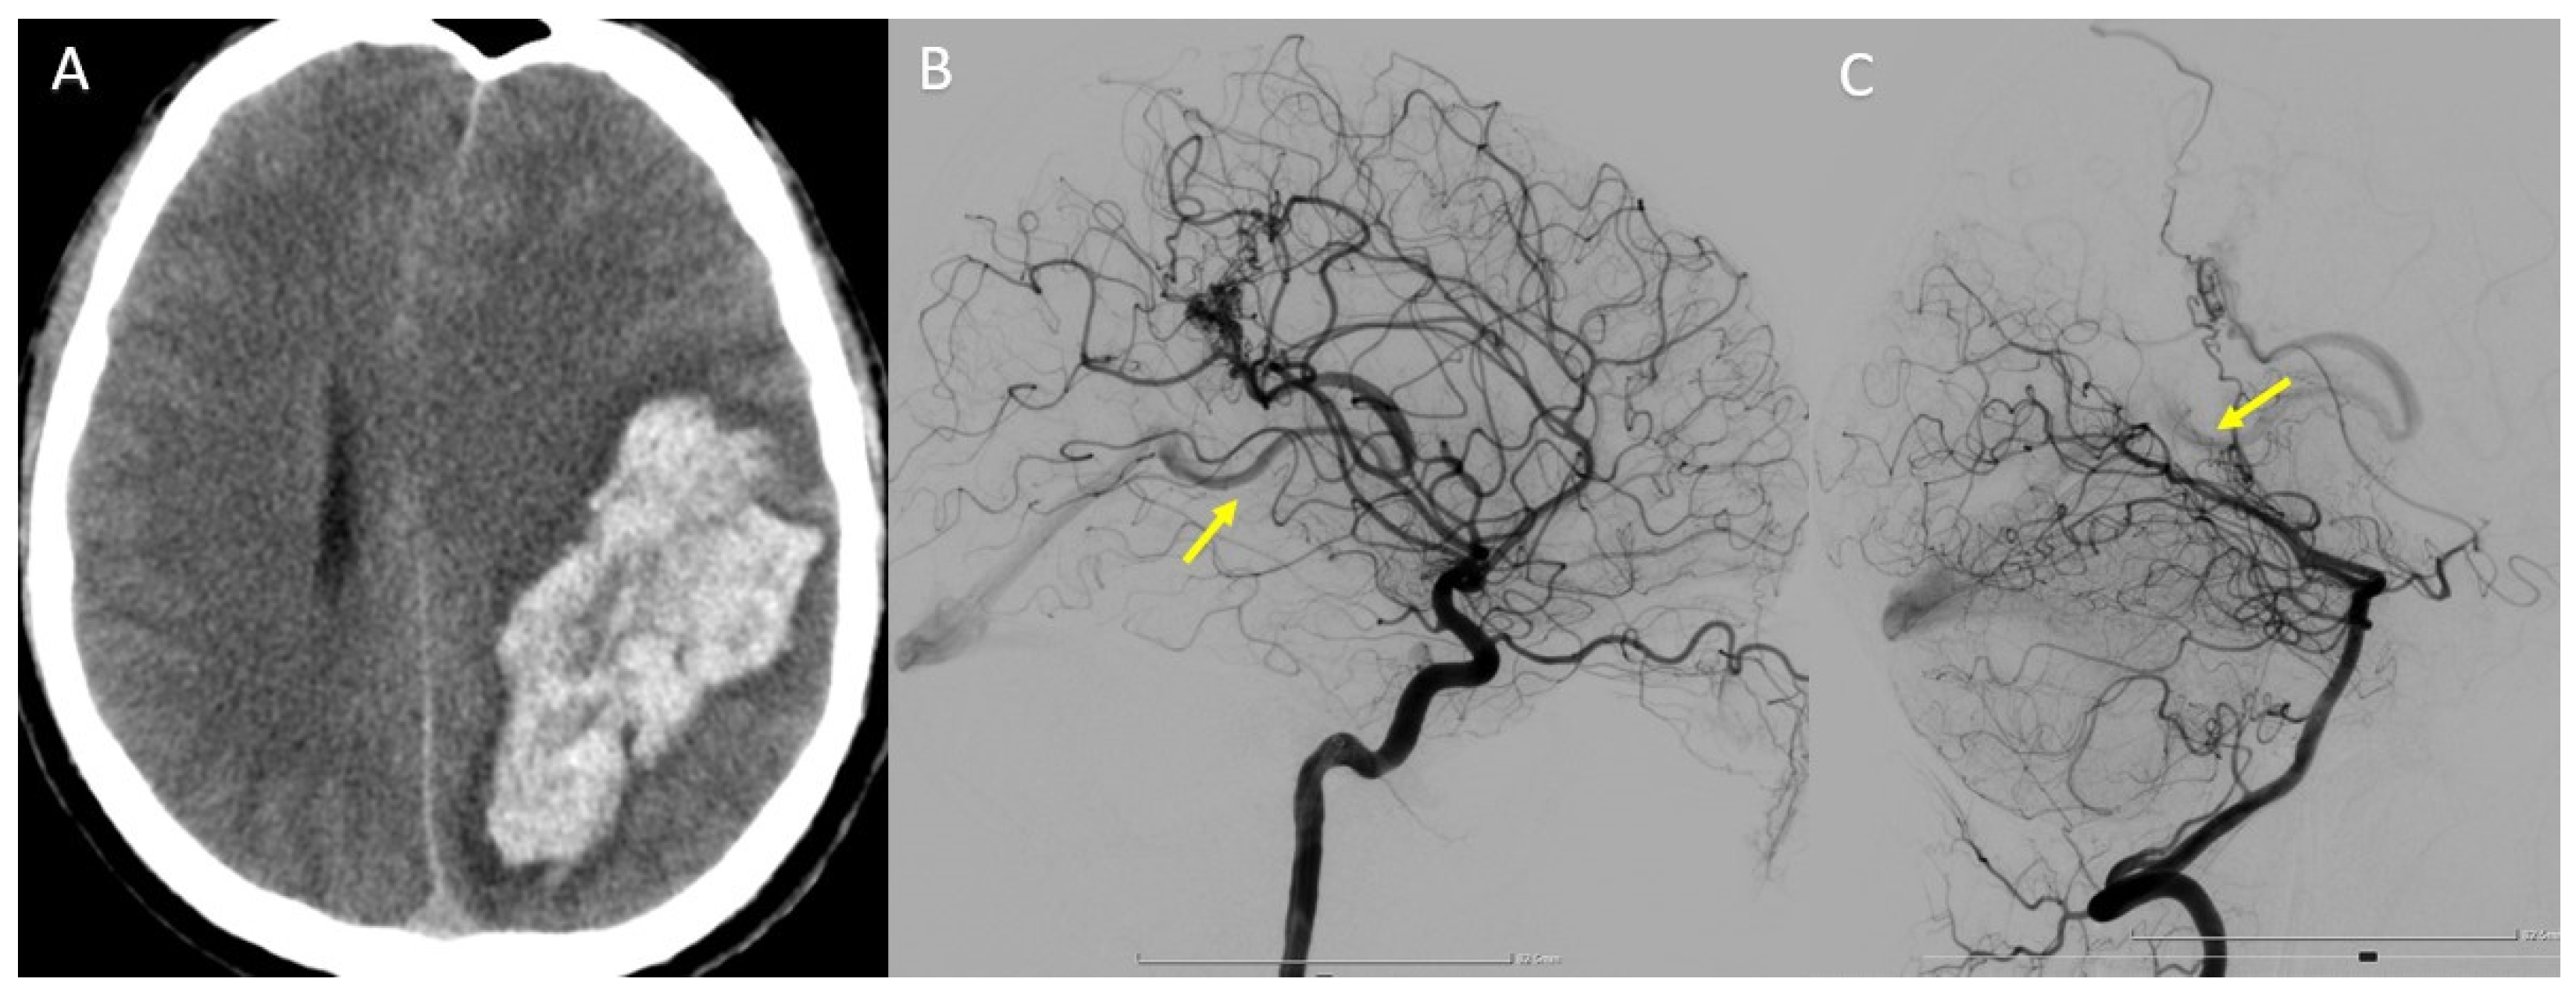

In this case, we present a 34-year-old patient who was diagnosed with temporoparietal parenchymal hemorrhage following a ruptured cerebral AVM (Figure 8A). DSA revealed that the nidus is supplied from two distinct vascular territories (Figure 8B,C).

Figure 8.

(A) Head CT scan—temporoparietal parenchymal hemorrhage. (B) Left internal carotid (ICA) DSA—lateral view. (C) Left vertebral artery (VA) DSA—lateral view. Yellow arrow—early filling of the deep venous system, and drainage to the great cerebral vein (of Galen).

In order to choose the best treatment strategy, a detailed analysis of the 3DRA images as well as the overlay between the two 3D volumes obtained by injecting both the left internal carotid artery and the left vertebral artery was required (Figure 9A–C). The analysis of the images showed that the arterial feeders originated from the left MCA and left PCA, while the deep venous drainage merges into the vein of Galen. The 3DRA imaging demonstrates the existence of multiple intranidal aneurysms, the largest being located near the feeder from the MCA.

Figure 9.

(A) Coronal MIP Overlay between the left ICA 3DRA (red) and left VA (blue). (B) Sagittal MIP Overlay between the left ICA 3DRA (red) and left VA (blue). (C) Axial MIP Overlay between the left ICA 3DRA (red) and left VA (blue)—nidus measurements. (D) MIP Overlay between the left ICA 3DRA and left VA—feeders targeted for endovascular occlusion. White asterisk—AVM nidus. Yellow arrow—AVM feeders targeted.

Considering the anatomy of the case, the treatment by catheterization of the branches going most directly towards the intranidal aneurysms (discovered during the diagnostic phase) was decided (Figure 9D). Thus, the analysis of the overlay between the two 3DRA volumes helped in the choice of an embolization strategy that allowed the exclusion of the AVM from the circulation by initial embolization of the nidal compartment at risk and secondary embolization of the remaining nidal compartment.

By using this overlaying software, the risks associated with the intervention were greatly reduced, and by accurately choosing the target vessels from which to embolize, the operating times, and therefore the radiation dose, were greatly optimized.